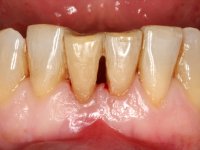

Female patient, 56 years-old, smoker. Teeth 41 and 31 with mobility grade III. Teeth 42 and 32 vital, with no mobility. After clinical and radiographic examination the extraction of central incisors was indicated.

Being an esthetic area it was decided to do an immediate splint of the crowns 41 and 31 to the adjacent teeth with a metalic mesh bonded in the lingual surface.